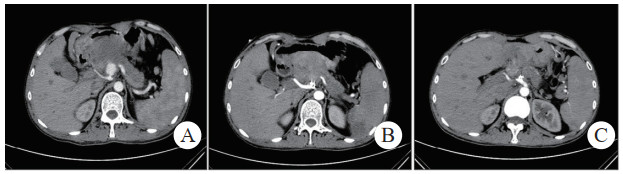

介入栓塞成功率为100%,术中栓塞后即刻复查造影显示,载瘤动脉或假性动脉瘤瘤腔不复显影及未见对比剂外溢,栓塞成功,见图 1(病例1)。

| 注:A、B为患者术前CT增强扫描,示胰腺炎影像,胰头下方血肿影像,中央可见与血管强化方式相同的动脉瘤影像(箭头示),其供血动脉为胰十二指肠上动脉;C为DSA示对比剂充满瘤腔并见对比剂外溢;D为DSA示介入栓塞术后,弹簧圈填满瘤腔及未见对比剂外溢 图 1 病例1术前、术后CT平扫及增强 |